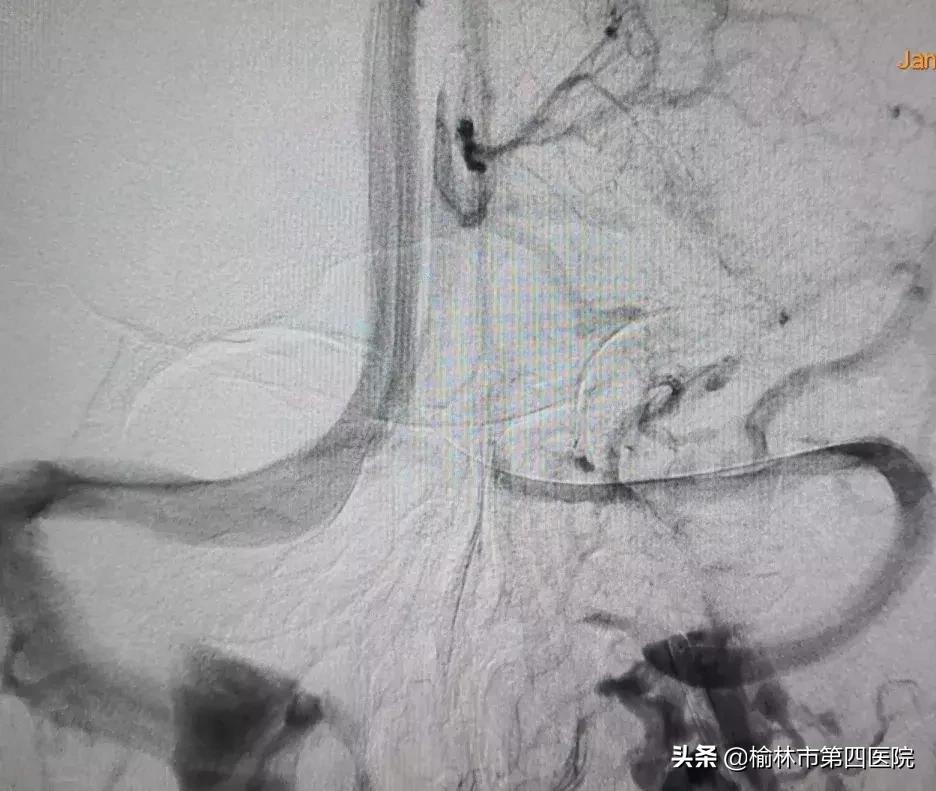

经过认真细致的准备,采取静脉麻醉下经股静脉入路的方案,术中股动脉造影导管和股静脉导引导管*管双**齐下,最终应用球囊序贯扩张左侧横窦狭窄段,因考虑到患者年龄较小,扩张后狭窄改善,故未予植入支架,为患者疏通了血流通道。

术后数天患者出院,腰椎穿刺压力接近正常,头痛、头闷症状消失,视力正常。